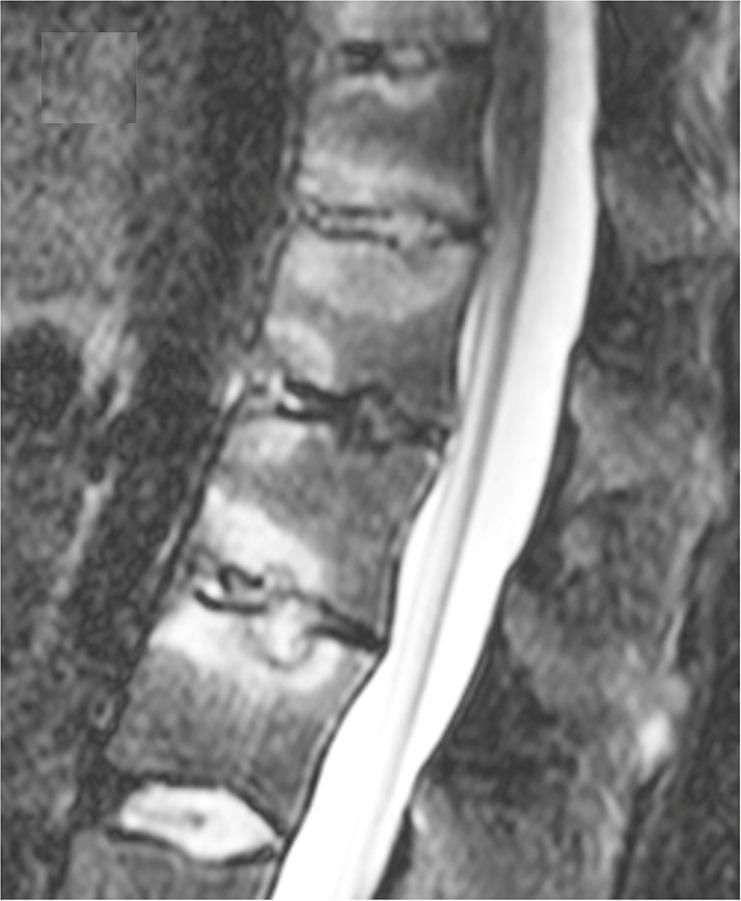

Cartilaginous endplate coverage of developmental Schmorl's node and the relevance of this in Schmorl's node etiology-based classification.

Quant Imaging Med Surg. 2024 Jun 1;14(6):4288-4303. doi: 10.21037/qims-24-335. Epub 2024 May 9.